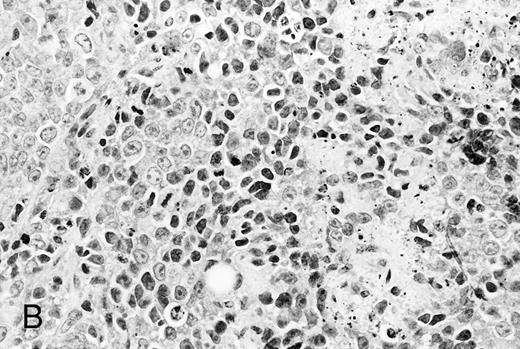

Histological analysis. The in vivo antitumor activity of anti-HM1.24 MoAb was further studied by histologic analysis of tumor-bearing mice that had been treated with either control IgG or anti-HM1.24 MoAb. In control groups of mice inoculated intravenously with ARH-77 cells, tumor cells proliferated mainly in the vertebral bodies and invaded the spinal cord and perivertebral tissues. In contrast, no tumor cells were found in the anti-HM1.24 MoAb-treated mice, surviving for 180 days. In SCID mice with advanced localized tumors, there was no evidence of metastases in other organs such as the liver, spleen, kidneys, lung, heart, stomach, and intestine by immunohistologic analysis using anti-HM1.24 MoAb. In the models with localized RPMI 8226 cells, tumor cells invaded the surrounding tissues including the muscle and showed typical morphologic features of neoplastic plasma cells, ie, irregular nuclear profiles with prominent nucleoli and abundant cytoplasm. Mitotic figures of the tumor cells were also identified. Neither necrotic areas nor infiltrating cells were found in the tumors of control groups (Fig 4A). In contrast, the tumors of anti-HM1.24 MoAb-treated mice showed many shrunk cells with picnotic nuclei. Necrotic areas and infiltrating cells were also observed in the tumors (Fig 4B). No tissue damage was found in the liver, spleen, kidney, lung, or heart in mice treated with anti-HM1.24 MoAb.

Histologic findings of RPMI 8226 tumors at day 25 after tumor inoculation. The subcutaneous tumors in SCID mice were removed 3 days after injection (100 μg/mouse) of (A) control IgG or (B) anti-HM1.24 MoAb. Necrotic areas and infiltrating cells were seen in the tumor from mice treated with anti-HM1.24 MoAb. Stained with hematoxylin and eosin. Original magnification ×130.